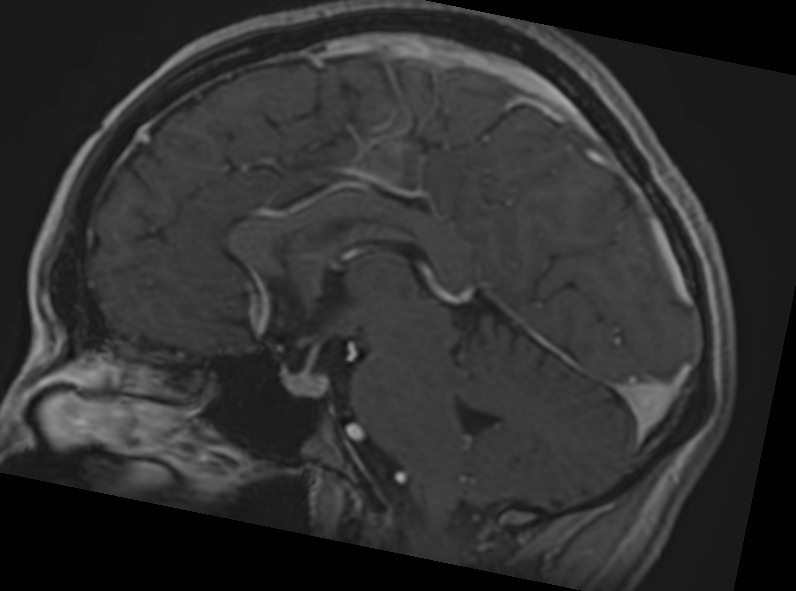

МРТ головного мозга с контрастированием – методика проведения магнитно-резонансной томографии, при которой внутривенно вводится препарат, содержащий гадодиамид (соли металла гадолиния). Контрастное вещество не проникает через гемато-энцефалический барьер и в норме не накапливается в тканях головного мозга. Однако при нарушении его целостности способно накапливаться в патологических очагах, в частности, в опухолях, зонах воспаления и участках демиелинизации нервных волокон.

Это способствует ранней диагностике заболеваний головного мозга, таких как рассеянный склероз, доброкачественные и злокачественные новообразования. Кроме того, с помощью контраста можно оценить степень и характер васкуляризации патологического процесса.

Исследование в нашей клинике выполняется на современном высокопольном томографе экспертного класса TOSHIBA VANTAGE TITAN 1,5 Тесла, который использует разные режимы сканирования с толщиной среза от 1мм в различных плоскостях с последующей цифровой обработкой полученных данных для создания трехмерных изображений. Аппарат позволяет выявлять структурные изменения в веществе головного мозга уже на начальной стадии, когда другие методы не дают результатов.